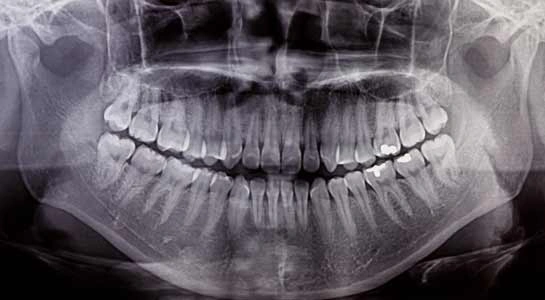

Wisdom Teeth In Winchester, VA

Wisdom teeth are also known as third molars. They usually start coming in between the ages of 17 to 21. They may become impacted if there is not enough space in your mouth for them to erupt fully. A wisdom tooth becomes impacted when it is blocked from pushing through the gums into your mouth. Wisdom teeth can also sometimes come in sideways or be tilted.

An Impacted Tooth Can Be Painless and You Might Not Even Realize It is There.

However, the gums covering part of or the entire impacted tooth can become infected causing swelling and pain. This is called pericoronitis. Sometimes you might even feel pain in your ear from an impacted wisdom tooth. The infection can spread down your throat or into your neck requiring you to be admitted to the hospital. An impacted tooth can sometimes get a cavity or cause a cavity on the tooth in front of it.